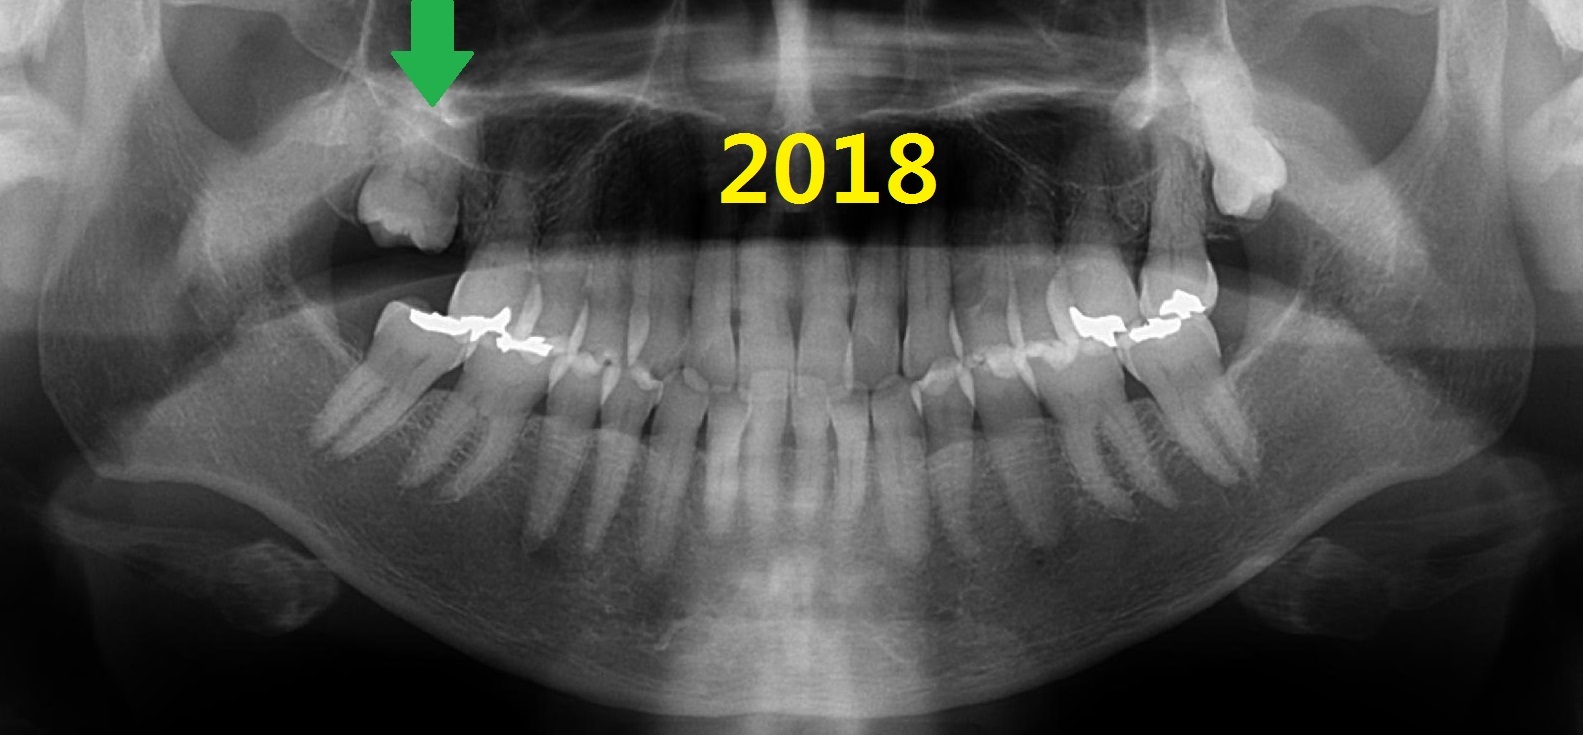

2018년(63세), 위 왼쪽 어금니가 아파서 내원함.

신경치료하고 씌움.

사랑니가 회전된 상태로 내원했지만 잘 사용하고 있음.